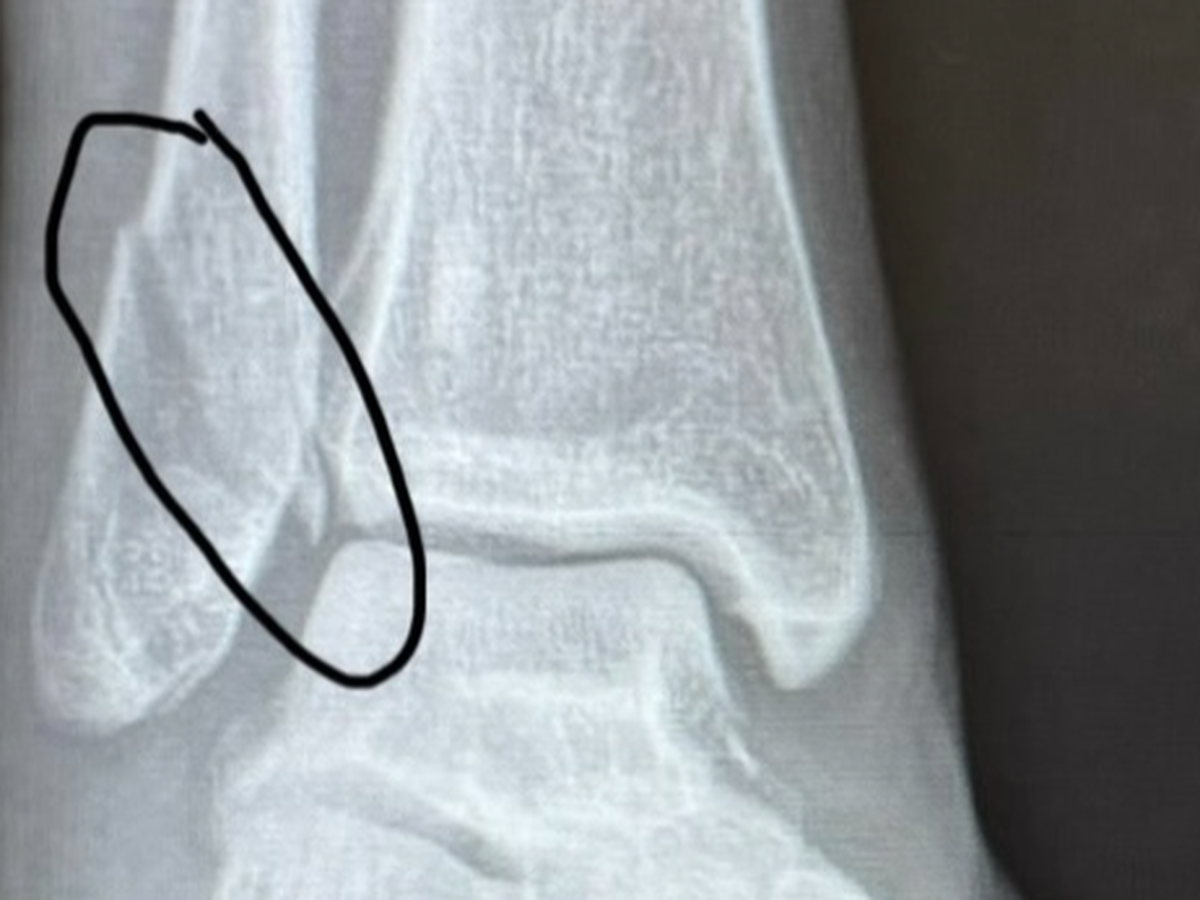

New findings-SEVEN ligaments in my ankle are torn. The bone will need re-broken, repaired and replaced. All ligaments

will need repaired. A scope will need done. 3 incisions.